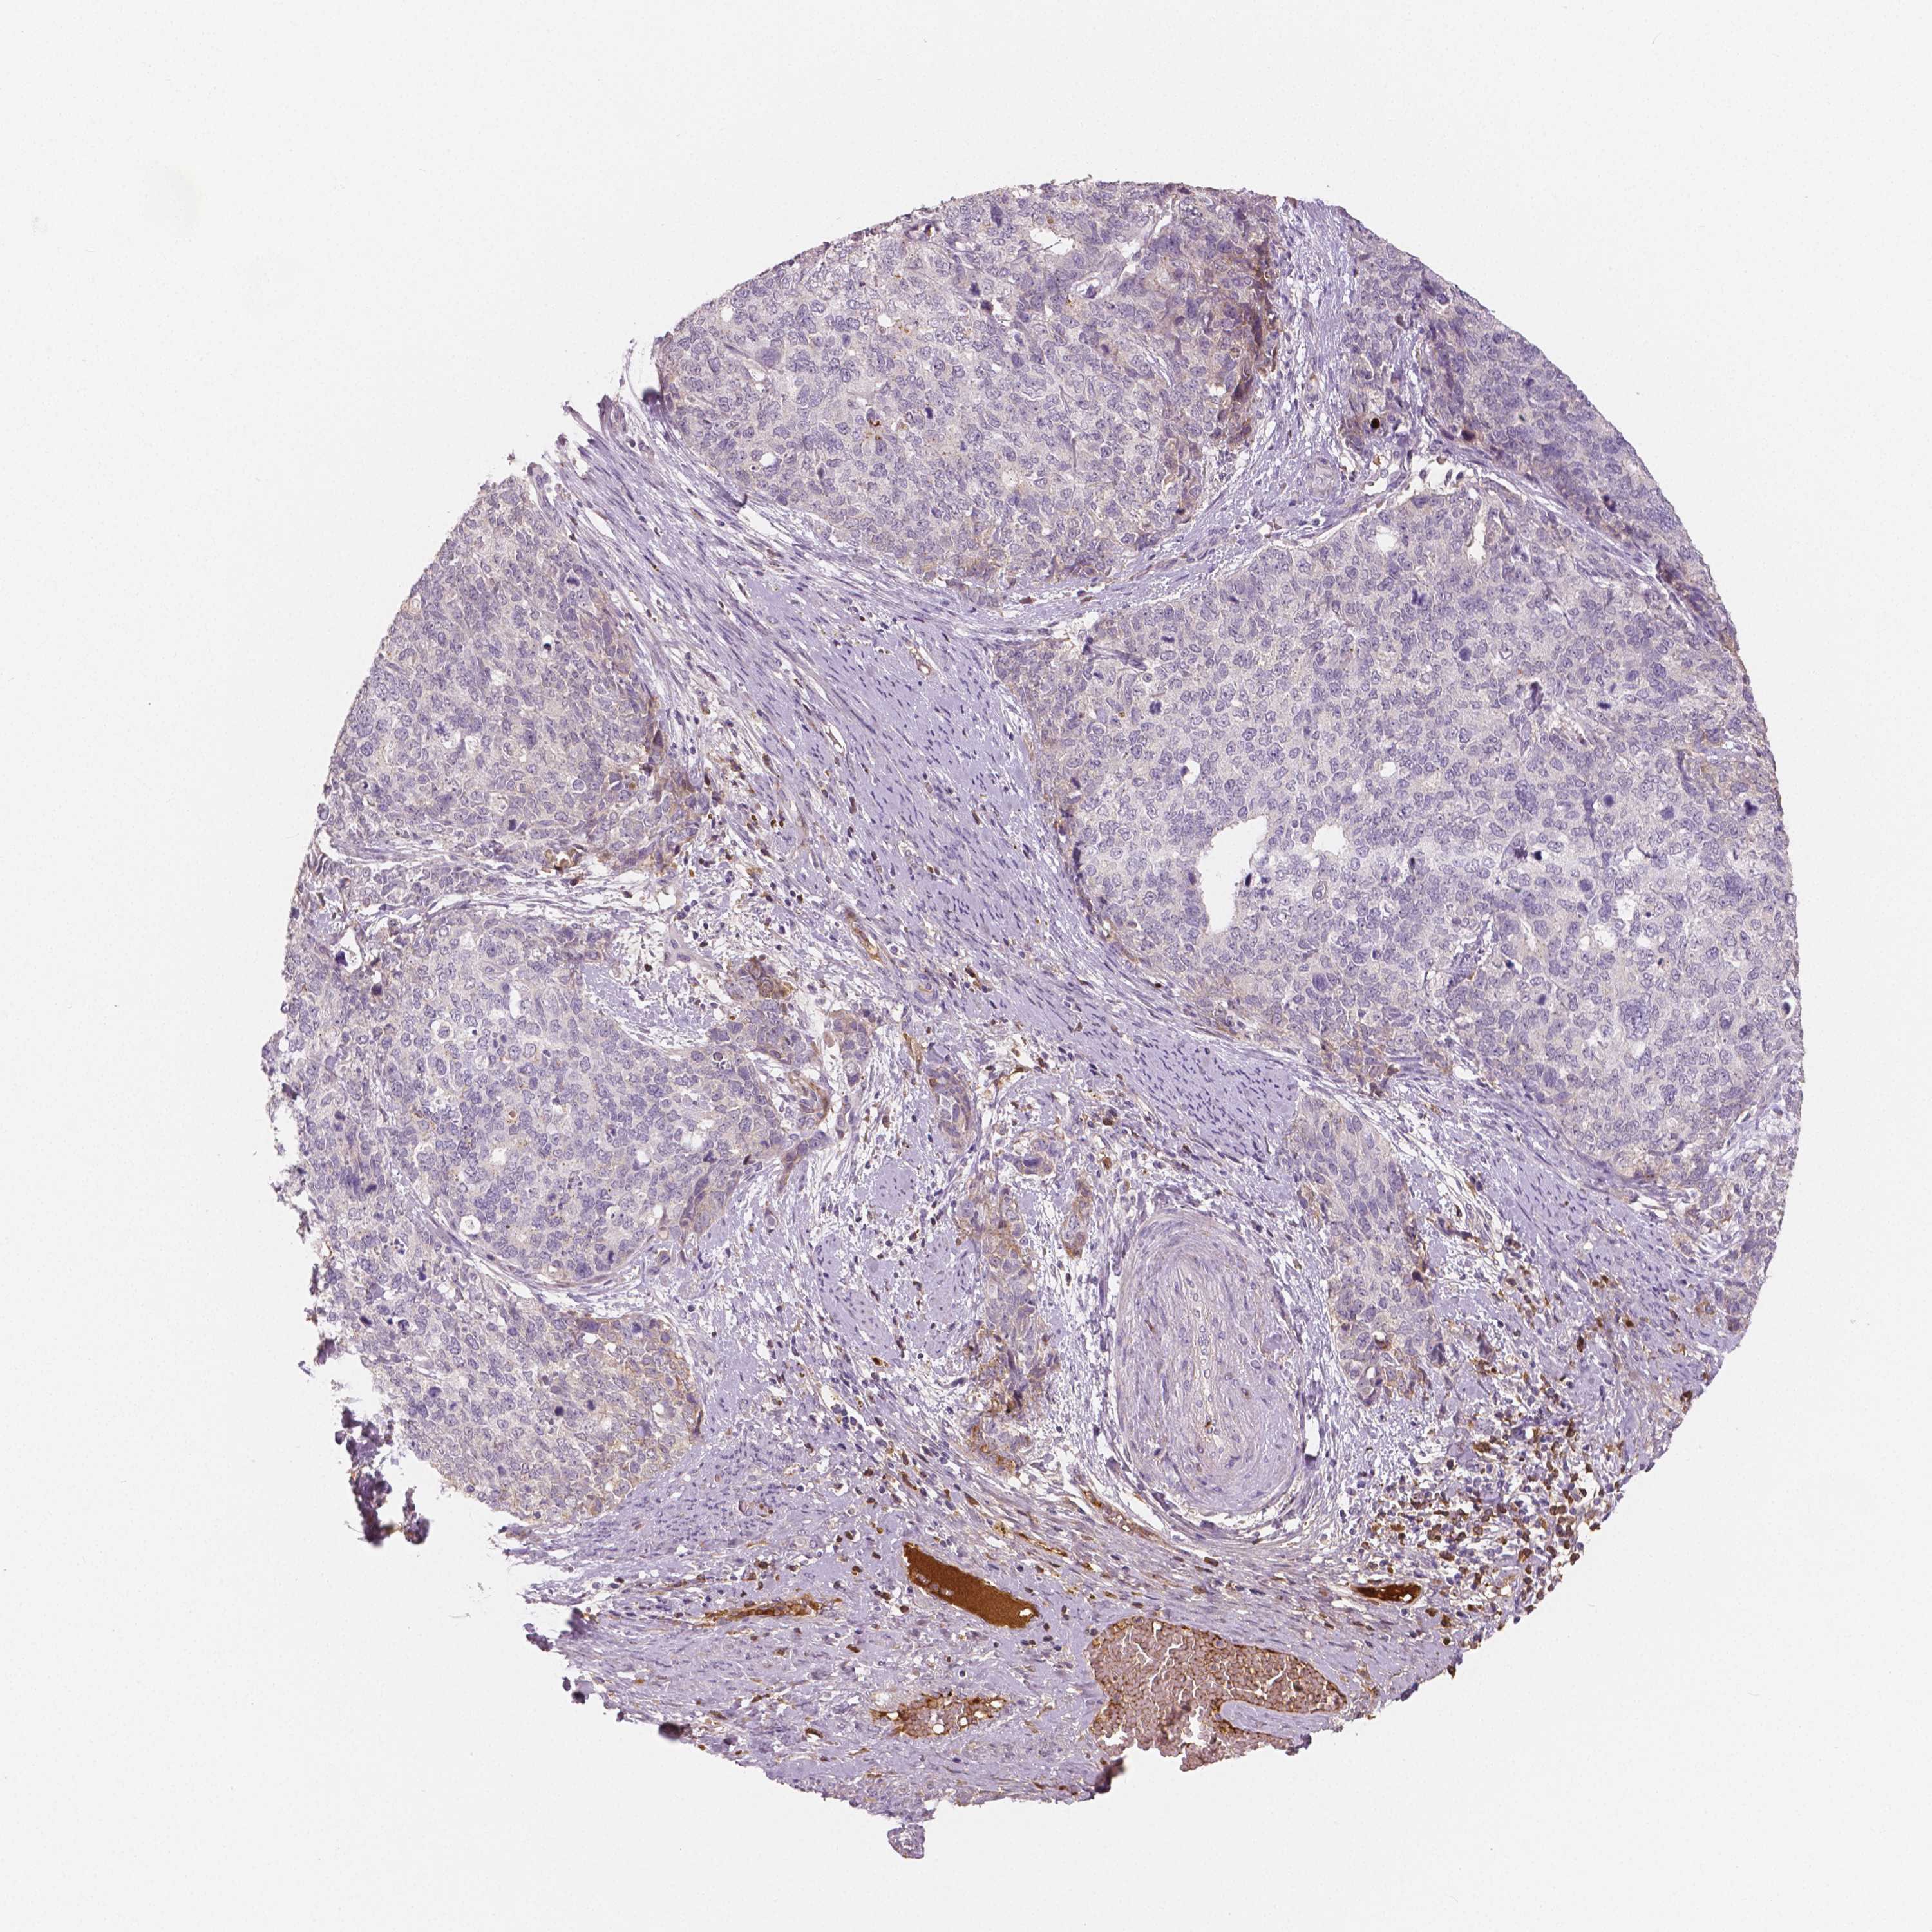

CERVICAL CANCER - Protein expressioni

A mouse-over function shows sample information and annotation data. Click on an image to view it in a full screen mode. Samples can be filtered based on level of antibody staining by selecting one or several of the following categories: high, medium, low and not detected. The assay and annotation is described here.

Note that samples used for immunohistochemistry by the Human Protein Atlas do not correspond to samples in the TCGA dataset.

Antibody stainingi

Antibody staining in the annotated cell types in the current human tissue is reported as not detected, low, medium, or high, based on conventional immunohistochemistry profiling in selected tissues. This score is based on the combination of the staining intensity and fraction of stained cells.

Each image is clickable and will lead to virtual microscopy that enables deeper exploration of all samples and also displays staining intensity scores, fraction scores and subcellular localization as well as patient and tissue information for each sample.

HPA001352

Squamous cell carcinoma, NOS

Adenocarcinoma, NOS